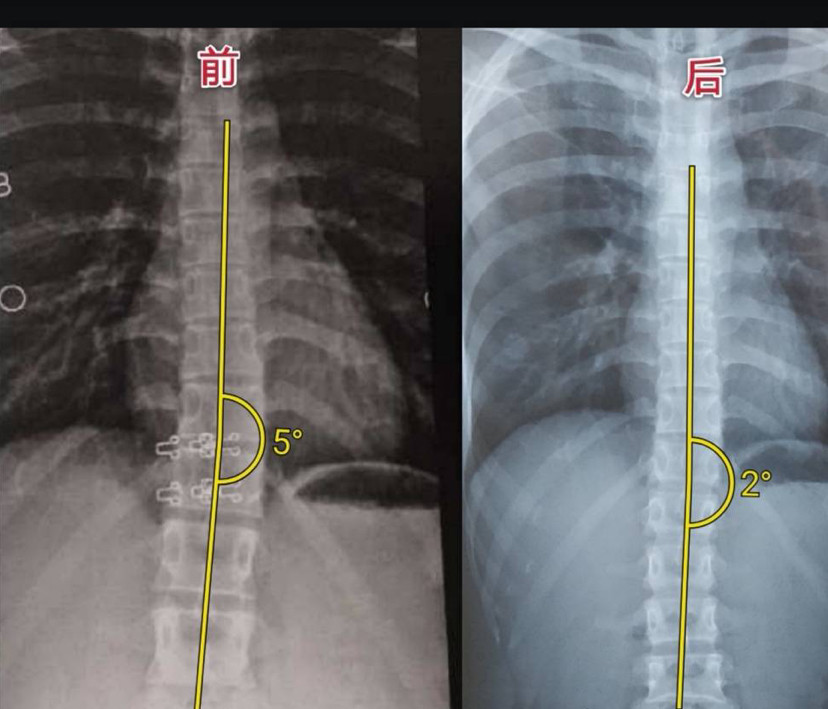

15岁侧弯女孩一次训练高低背减3度效果不错

图片尺寸1284x802